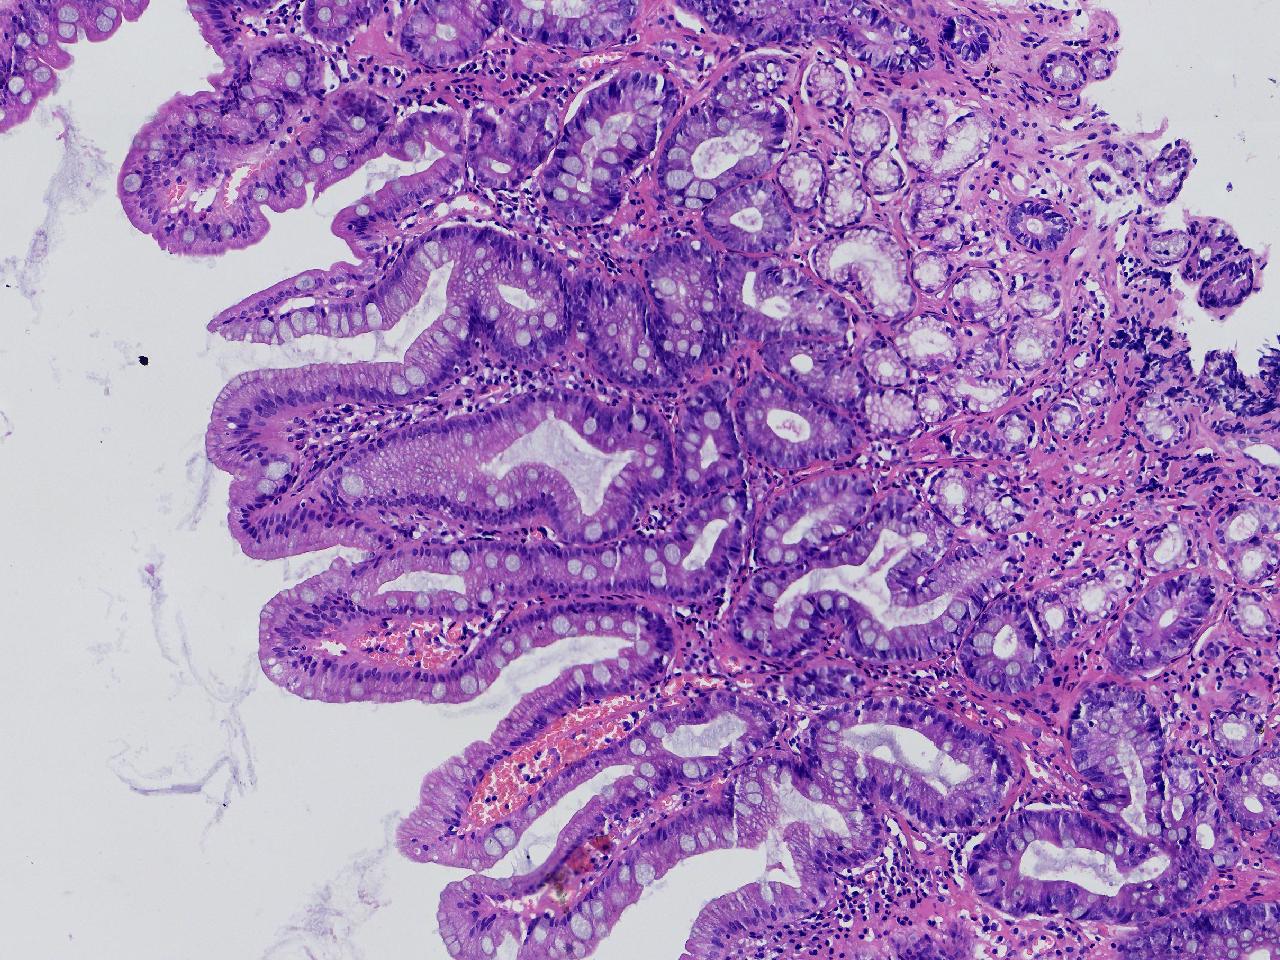

1.间质内淋巴组织有问题吗? 2.有没有低瘤变?

一般病史男,65岁,胃镜活检,胃窦粘膜红白相间,花斑样改变,大弯侧粘膜变薄,血管透见,可见多发片状充血糜烂灶及点状褐色物覆着,活检2块送检,质软弹性可。

标本名称胃窦活检

大体所见灰白色不整形软组织2块,直径均0.2厘米。

慢性萎缩性胃炎伴肠化,固有层淋巴细胞聚集

萎缩性炎,伴有肠化,淋巴组织挤压变形,感觉没有太大的问题。

炎性,无瘤变。